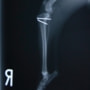

■ 症例22 ポメラニアン 1歳5か月 去勢雄

左後肢の挙上を主訴に来院した。整形学的検査、レントゲン検査より左右の膝蓋骨脱臼(左GradeⅡ〜Ⅲ、右Grade Ⅱ)を認めた。また、脛骨の前方引き出し試験の際に、引き出し兆候は認められないものの、疼痛が認められたため、前十字靭帯の損傷が疑われた。術中における、目視および関節内の操作によって、前十字靭帯の損傷や過伸展といった異常が認められなかったため、膝蓋骨脱臼の整復のみ実施した。手術手技は縫工筋及び内側広筋の解放、脛骨粗面の外側転位、滑車ブロック形造溝術、内外側関節包の縫縮を実施した。本症例は跛行もなく経過良好である。しかし、頸骨高平部の角度(TPA)が 右26.2°、左24.9°であり、解剖学的に前十字靭帯損傷のリスクが高いことから今後の経過に注意が必要である。